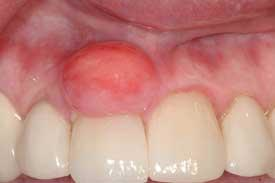

Notes and findings: The patient is a 51-year-old white female maintenance patient who has not had a dental appointment in over two years. She scheduled an appointment because a large growth is noticeable in the anterior region of her mouth, and this lesion has her concerned. The patient reports that the growth has been there for over one year and has grown considerably during that time. As the oral tissues are assessed, it is noted that the large lesion in the anterior is firm, smooth, and sessile (broad-based). The patient reports no pain, but does report that the growth can become somewhat ulcerated if she brushes too hard or traumatizes the area (see Figure 1).

Perioral and intraoral characteristics: The lesions are normally found on the attached gingiva. The abundance of tissue is usually the same color as the surrounding tissue, with a smooth surface. Sometimes the surface may be more textured, depending upon the existing oral forces and location in the patient’s mouth. Additionally, the surface epithelium may be more of a dark color depending upon the amount of trauma and inflammation that is produced with the lesion.